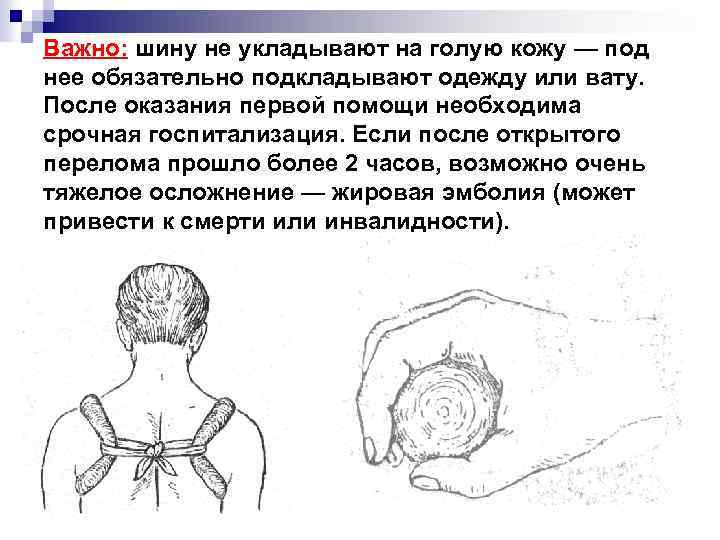

Важно: шину не укладывают на голую кожу — под нее обязательно подкладывают одежду или вату. После оказания первой помощи необходима срочная госпитализация. Если после открытого перелома прошло более 2 часов, возможно очень тяжелое осложнение — жировая эмболия (может привести к смерти или инвалидности).

Важно: шину не укладывают на голую кожу — под нее обязательно подкладывают одежду или вату. После оказания первой помощи необходима срочная госпитализация. Если после открытого перелома прошло более 2 часов, возможно очень тяжелое осложнение — жировая эмболия (может привести к смерти или инвалидности).